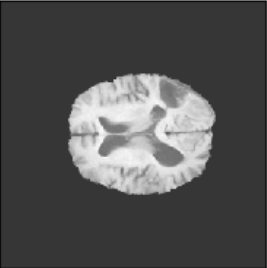

To illustrate the performance of the proposed technique for clinical applications, MR images were chosen. The performance of the technique was tested by registering multi-modal MR image pairs. In a clinical setup, it is common practice to register images or volumes acquired from different imaging modalities or MR sequences. Figure 3 illustrates the degree of overlap between moving images (a) T2 and (f) T1 weighted sequence on fixed images (b) T2 and (g) T2 weighted sequence respectively. It was observed using the registration proposed in this manuscript, the dice score improved from 0.44 (prior to registration) to 0.91 (post registration) for multimodal sequences. On the BraTs data, figure 4 (a-d) illustrates the performance of our method based on other metrics such as Dice, SSMI, MI, and MSE respectively. As the key points were generated by utilizing only the feature maps of the initial two layer of the network, the spatial dimension of the data has little impact on the performance. Unlike other CNN based technique which considers the entire image for estimating the transformation parameters, our method requires CoMs which reduces the dimensionality from (m n n) to (m 2), where m denotes the number of feature maps and n is the pixel dimension of the feature map. This aids in lowering execution time drastically. The proposed pipeline also consists of an uncertainty estimator. uncertainty maps illustrated in all the above examples show the region of higher variance in registration, which in turn suggests surgeons/ observers to make better decisions. Pixel region with red color indicates the larger variance region while blue indicated low variance region. For example in figure 3 (e) shows that the central region of the brain has higher pixel-wise variance as compared to the outer part of the brain. The performance of the algorithm on volumes on the same modality is illustrated in figure 3 (a-e)